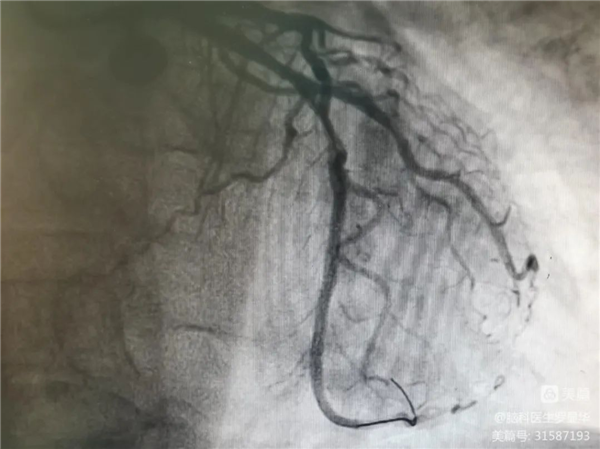

支架植入后狭窄完全解除